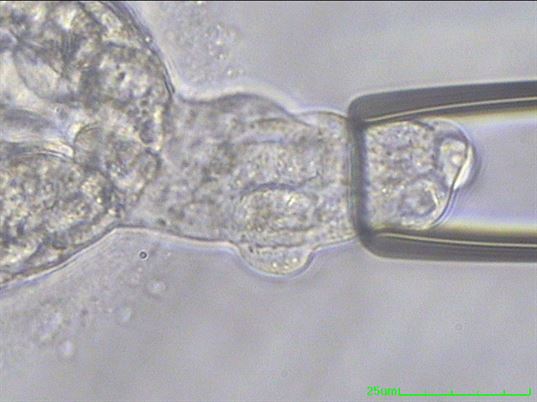

Günümüzde ileri anne yaşı, şiddetli erkek faktörü, tekrarlayan tüp bebek başarısızlıkları ve tekrarlayan gebelik kaybı gibi pek çok farklı endikasyon ile preimplantasyon genetik tanı olarak da bilinen PGT-A yöntemi uygulanmaktadır (Resim 1).

Resim 1: Preimplantasyon genetik tanı için yapılan trofoektoderm biopsi işlemi